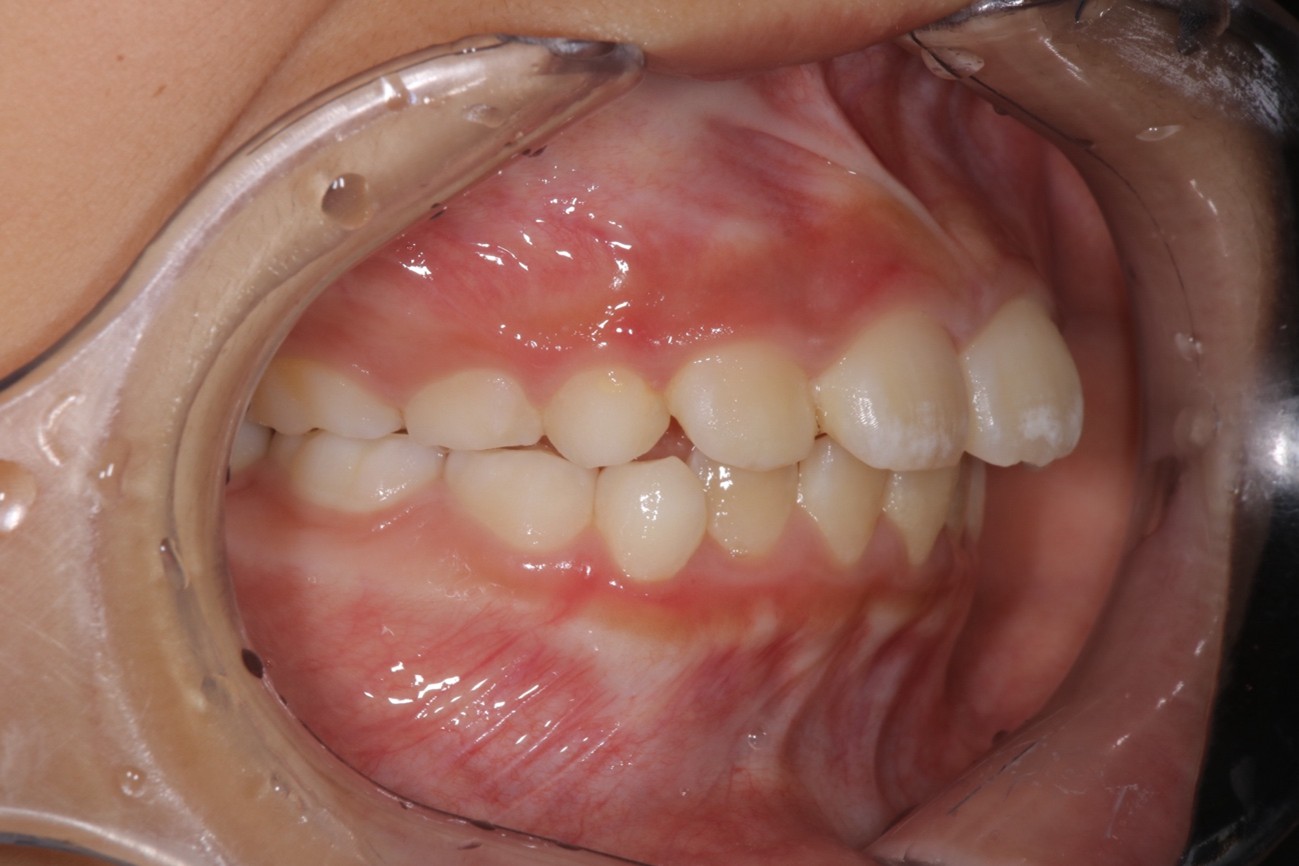

Before